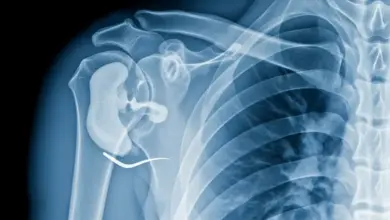

A escápula alada, caracterizada pelo afastamento anormal da borda medial da escápula em relação à parede torácica, afeta aproximadamente 1 em cada 7.500 pessoas, segundo dados do Hospital das Clínicas de São Paulo.